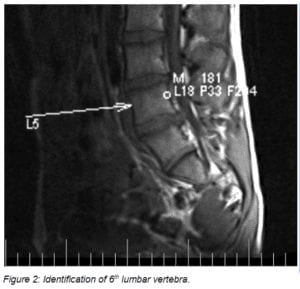

Magnetic Resonance Imaging (MRI) Imaging was available at the January visit and demonstrated prominent protrusions at two levels. See Figures 2 to 4

The physical therapists and pain physician helped the parents identify an appropriate pediatric surgeon at a well-known medical center in a large metropolitan area. A consult was obtained within 2 weeks. The surgeon requested a 6-week trial of 15 mg. oral Meloxicam. This brought no change in symptoms and laminotomy and microdiscectomy on left L5-L6 and right L6-S1 surgery was performed in March 2015.